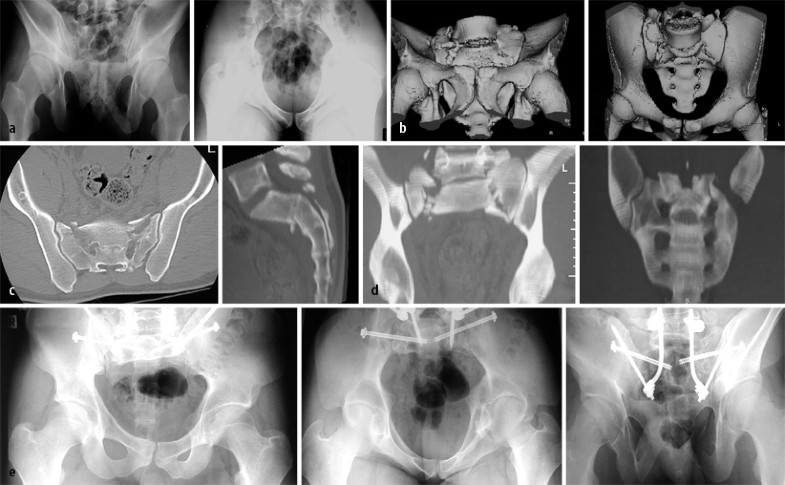

Neben der klinischen Untersuchung ist die konventionelle Röntgenbilddiagnostik die Standardbildgebung (Ausgangsbild) und bleibt dies vorläufig auch. Auch in der Zeit der vielzeiligen Spiral-CT mit multiplanarer Rekonstruktion erscheint das a.-p. Röntgenbild des Beckens bis auf weiteres unverzichtbar zur Erstbeurteilung [13]. Insbesondere, wenn eine umgehende Indikation zur CT gestellt wird, wird die nahe Zukunft zeigen, inwieweit die typischen Standardserien (a.-p. plus Ala- und Obturatoraufnahme bei der Azetabulumfraktur, a.-p. plus Inlet- und Outlet-Aufnahme bei Beckenringverletzungen; Fall 1, Abb. 1, Fall 2, Abb. 2) durch die entsprechenden CT-Rekonstruktionen ersetzt werden können (Fall 2, Abb. 2). Volumenorientierte 3D-Rekonstruktionen bieten eindrückliches Bildmaterial, können bei geringer Dislokation der Frakturen aber die Frakturerkennung erschweren [22]; zur Bewertung der eigentlichen Pfannenregion ist bei Azetabulumfrakturen das „Herausrechnen“ des Femurkopfs nötig.

Fall 2, 21-Jähriger mit isolierter bilateraler transforaminaler Sakrumfraktur AO 61C3.3), a Outlet- und Inlet-Aufnahme, b 3D-Oberflächenrekonstruktion in analoger Projektion, c CT-Nativschnitt und sagittale 2D-Rekonstruktion, d volumenorientierte Rekonstruktion, e a.-p., Inlet- und Outlet-Aufnahme nach Versorgung mit triangulärer bilateraler spinopelviner Transfixation, weitere Erläuterungen s. Kasuistik

Bei dem 21 Jahre alten Mann lag eine isolierte bilaterale transforaminale Sakrumfraktur AO 61C3.3 („blow-out-fracture“) vor. Die Diagnose erfolgte mittels Outlet- und Inlet-Aufnahme, 3D-Oberflächenrekonstruktion in analoger Projektion, CT-Nativschnitt und sagittaler 2D-Rekonstruktion sowie volumenorientierter Rekonstruktion (Abb. 2 a–d).

Nach Reposition wurde die Verletzung mit triangulärer bilateraler spinopelviner Transfixation versorgt (Abb. 2 e).